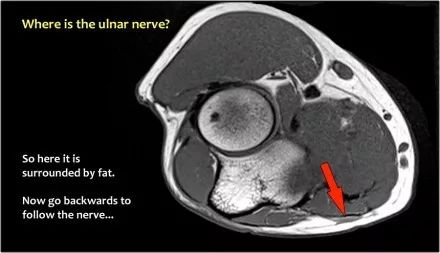

尺神经:在这里,我们看到了肘管内的尺神经。尺骨侧支带的后带形成隧道的底部,而支持带形成屋顶。

该患者有尺神经神经病变。肘管综合征是一种常见的周围神经病变。它产生于肘管内尺神经,其中该神经传递肘管支持带的下方的压缩。

当他们将尺神经带出隧道时,他们把它放在哪里,它可以是皮下,肌肉下或肌肉内。

因此,当我们回到图像时,您会发现很难找到神经。任何这些皮下结构都可以是转位神经。一种方法是远端跟随结构,直到你发现远端的尺神经位于由脂肪包围的前臂近端的正常位置。然后当你向近端跟随它时,你会发现这是皮下移位。

在这种情况下,有神经炎。神经增大。在T2W图像上有高信号。另一个标志是在矢状图像(箭头)上看到的束的不均匀扩大。